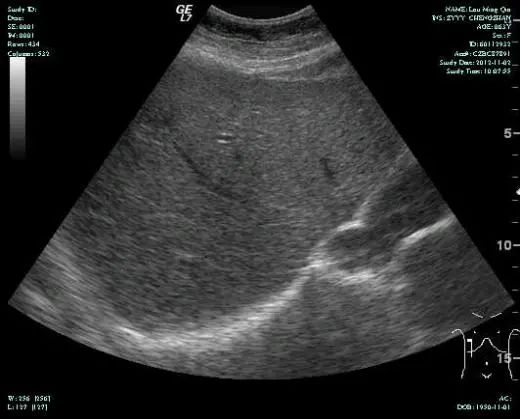

影像学表现:

CT-T

CT-H1

MR-H1

影像学检查结果评估:cPD。